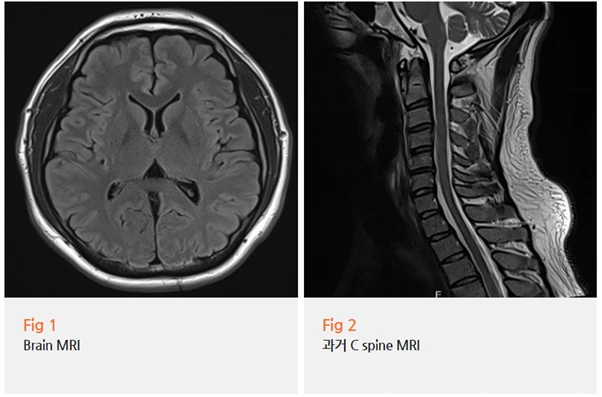

뇌 MRI를 먼저 시행했고,

다행히 뇌에서는 특이 소견이 없었어요.

그런데 저는 거기서 멈추지 않았어요.

뇌 MRI가 정상이라는 결과를 보는 순간,

저는 자연스럽게 다음 가능성으로 시선을 옮겼어요.

목이에요.

상부 경추, 그러니까 목 위쪽 부분의 기능장애는

두경부 주변 근육들의 과활성화를 불러일으키는데요,

그 영향이 눈 주변 근육까지 이어질 수 있어요.

이 환자분의 경우 우측 후두부와 측두부 두통이 함께 악화된 점,

그리고 목 MRI에서 상부 경추의 기능장애가 확인된 점이

이 판단을 뒷받침해줬어요.